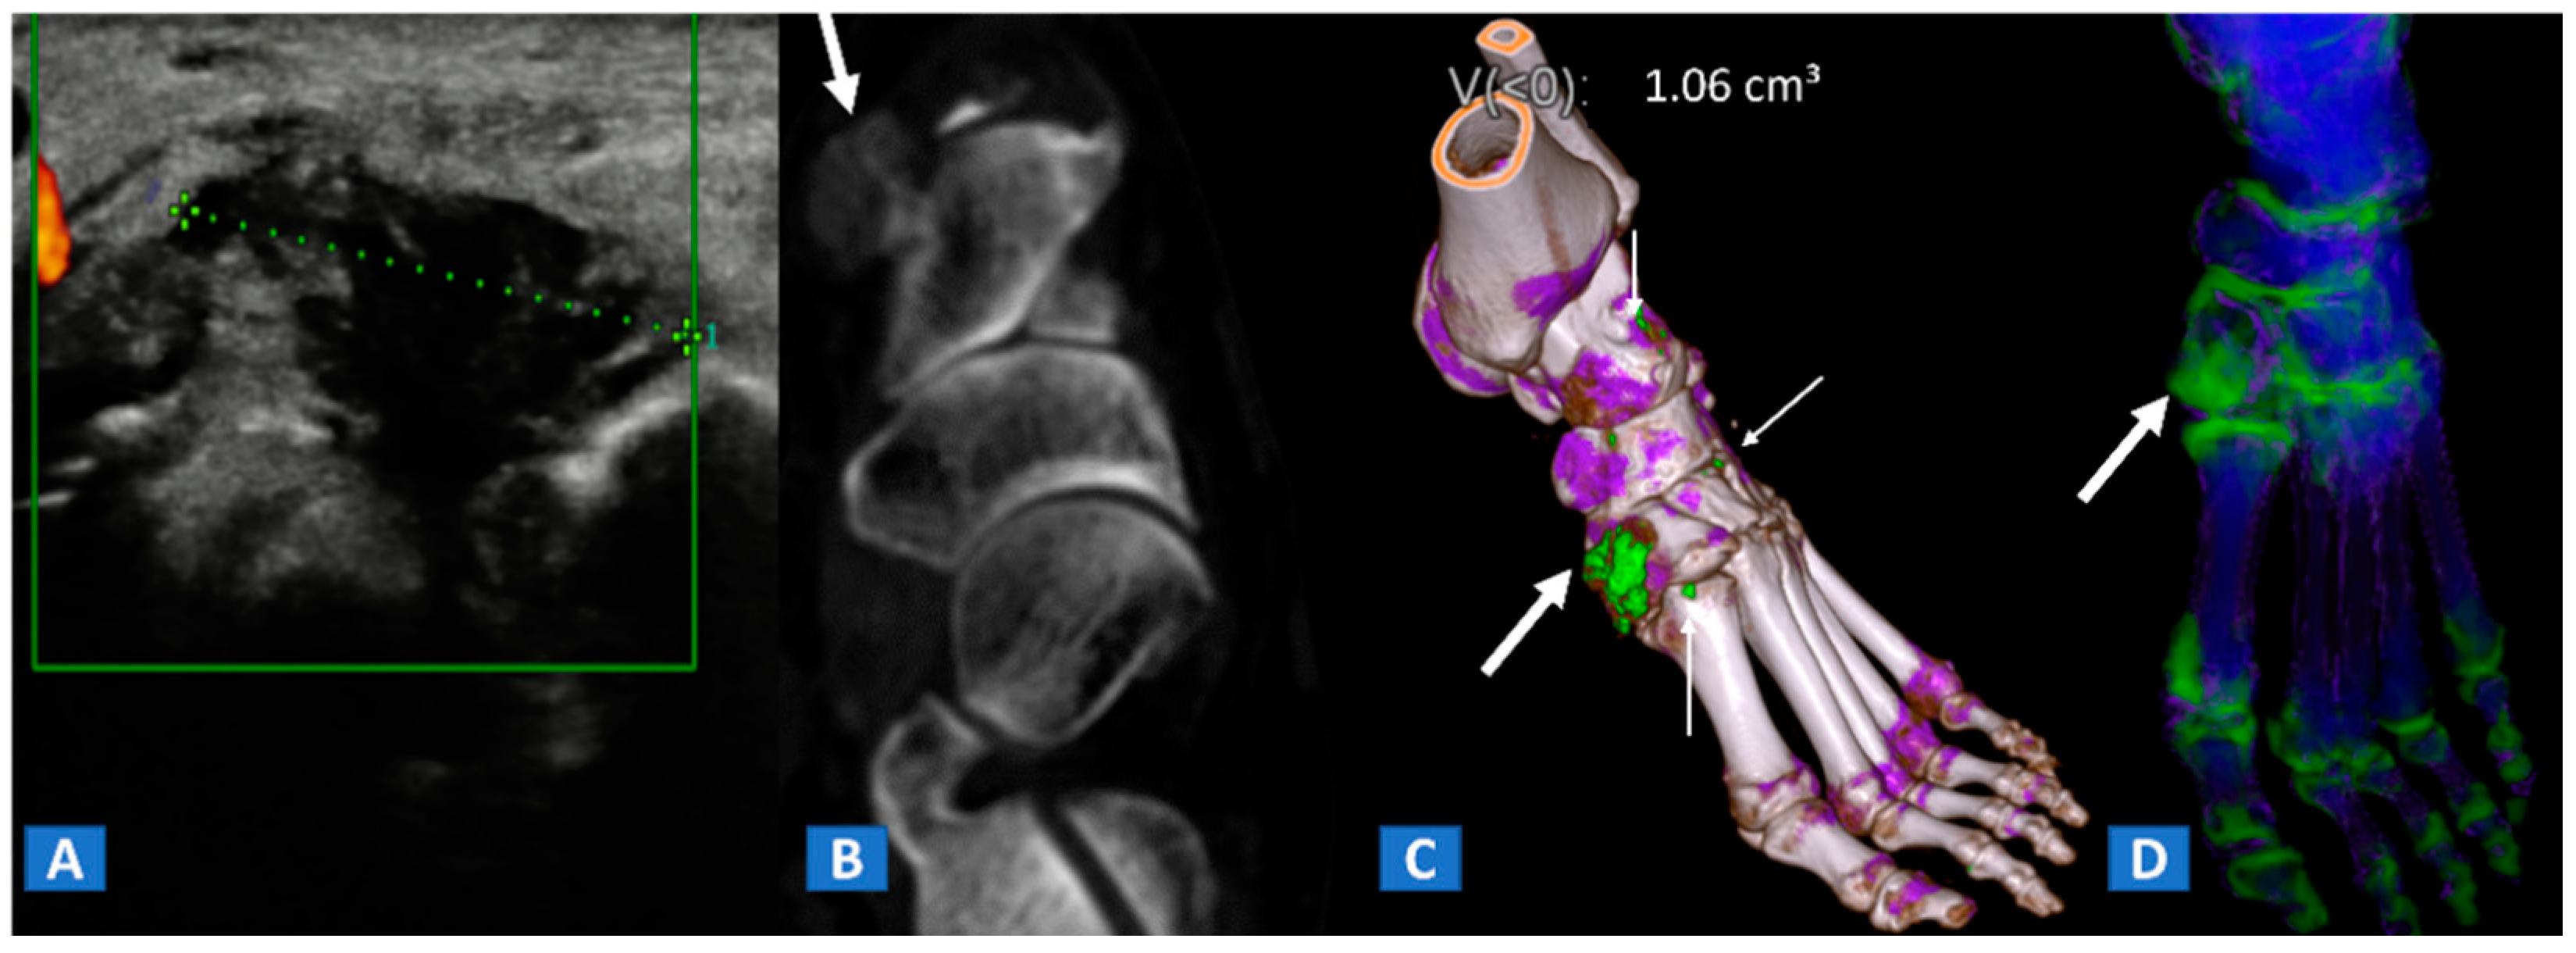

6. Non-Traumatic Osteochondral Lesions